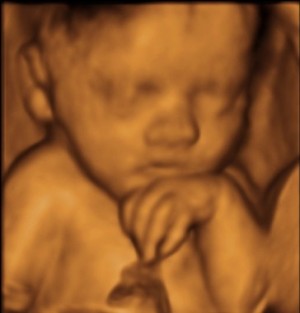

The Baby Scan Company offer range of packages from 2D-4D from Tay Medispa in Per

Tay Medispa in Perth now offer a range of specialist antenatal services.